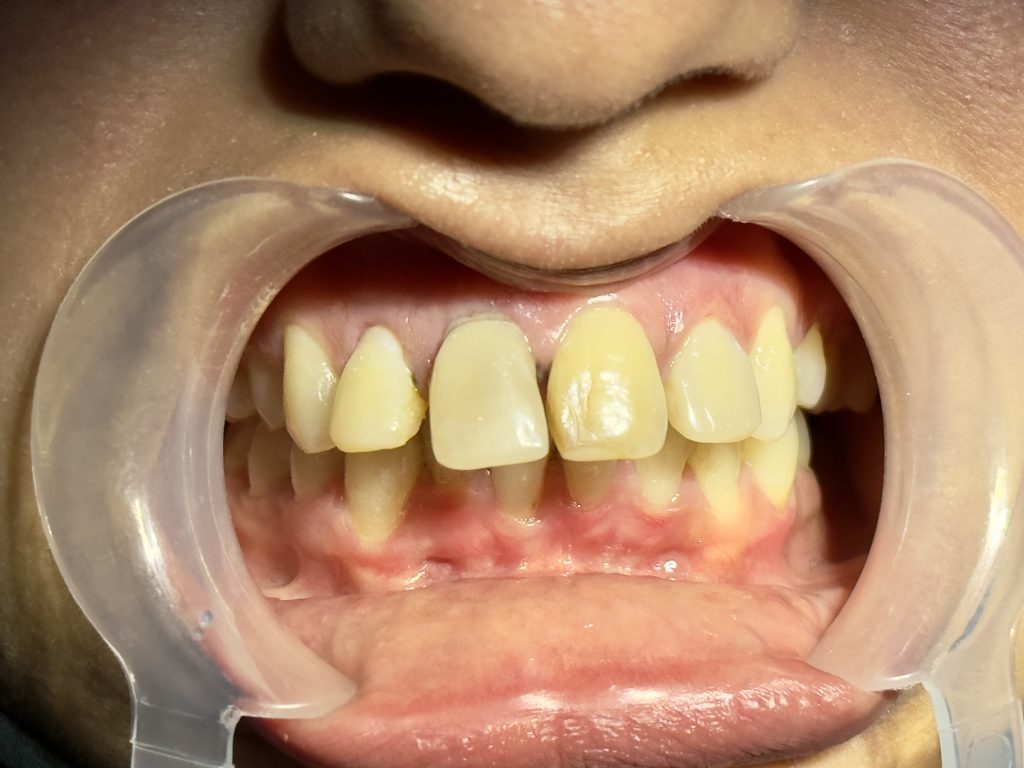

“I don’t like my smile. My front teeth are discolored and uneven. I want a natural and beautiful smile, but I cannot go for braces.”

- Moderate discoloration of tooth #11 and #21.

- Slight midline discrepancy; patient declined orthodontic correction.

- Post-traumatic discoloration due to pulpal necrosis.

- Asymmetrical incisal edges, smile cant, and uneven gingival margins.

- Reduced incisal guidance.